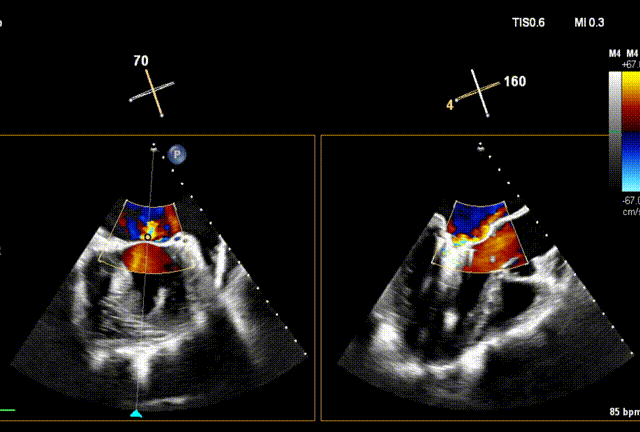

术前经食道超声(TEE)评估

术前TEE

DMR P2脱垂连枷(脱垂范围:12mm,连枷间距:3mm),反流2区,MR重度(VC:4* 10mm),A2:21mm,P2:10mm,AP:30mm,MVA约 4.7 cm²。